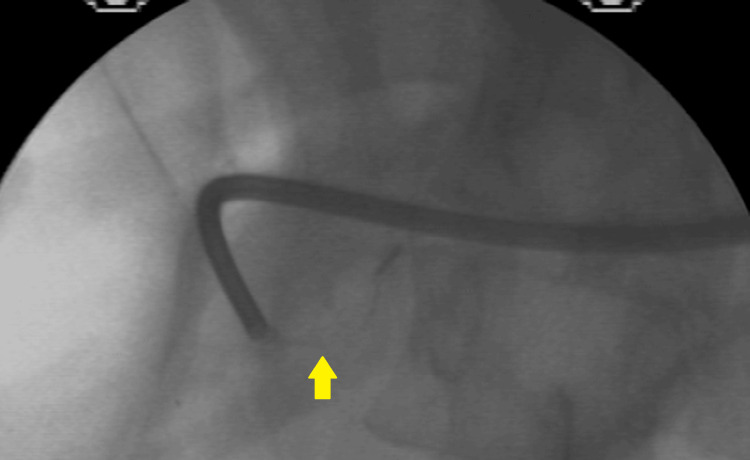

A sphincterotomy was performed (Figure 4), followed by dilation of the distal CBD using a 15-mm balloon catheter (Figure 5).

However, stone removal with a stone-extraction balloon was unsuccessful (Figure 6).